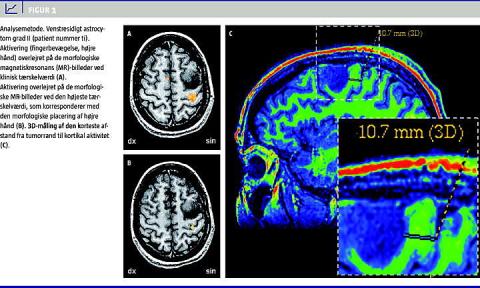

Til brug i den kirurgiske planlægning blev der fremstillet billedserier i tre projektioner gennem hele hjernen med aktiveringen overlejret på de morfologiske billeder ved en statistisk tærskelværdi, der af neuroradiologen var afpasset klinisk brug (Figur 1A ). For hvert enkelt paradigme i vores picture archiving and communication system (PACS) blev disse billedserier gemt elektronisk som præsentationer, så de var let tilgængelige for kirurgerne både præ- og intraoperativt.

Vi udviklede en standardiseret målemetode, som både tog hensyn til morfologien og fMRI-aktiviteten. Først blev der fremstillet billeder med så høj en tærskel, at der kun kunne registreres aktivitet på et aksialbillede pr. paradigme svarende til det område, hvor man ud fra morfologien ville forvente aktivitet (Figur 1B). Derefter blev punktet markeret på den aksiale anatomiske FSPGR-sekvens i programmet GE-Reformat version 4.2. I det skrå 3D-vindue kunne den direkte afstand mellem fMRI-aktiviteten og tumorranden nu måles. Ved at rotere omkring punktet for fMRI-aktiviteten kunne afstanden til tumorranden finjusteres, indtil man fandt den korteste afstand (Figur 1C). Metoden er ikke 100% objektiviseret, men har gennem et internt interobserverstudie vist en høj grad af reproducerbarhed (coefficient of reproducibility 2,4 mm).